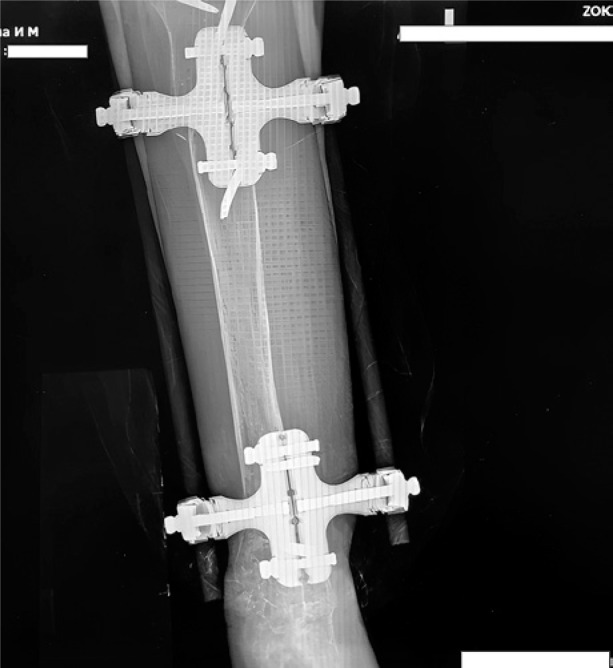

骨折延迟愈合是骨科实践中常见的并发症,尤其是骨质疏松症患者。再生医学的进步,包括间充质干细胞(MSCs)在基质血管部分,引入了新的治疗方法来解决这一挑战。本病例描述了一位患有绝经后骨质疏松症和左下肢先天性异常的患者,其胫骨近端骨折伴碎片移位。骨质疏松治疗开始,骨折使用外固定和压迫处理。尽管在8个月的时间里骨密度有所改善,但x线评估显示没有骨折愈合的证据。因此,在骨折部位进行局部给药联合针刺,然后进行一系列自体浓缩血浆(ACP)注射。3个月内,观察到骨痂形成的影像学征象,最终在开始再生治疗6个月后骨折完全愈合。尽管我们临床病例数量有限,无法对骨折愈合的主要促进因素得出明确的结论,但现有文献表明,骨折部位高浓度内源性资源的动员促进了组织再生。身体活动和辅助药物治疗进一步促进了这一过程。结合MSCs和acp衍生生长因子的再生疗法是治疗系统性骨质疏松患者骨折并发症的一种有希望的辅助方法。这种策略有可能促进骨愈合,同时可能延迟甚至避免需要更多的侵入性手术干预。

Delayed fracture union is a common complication in orthopedic practice, particularly in patients with osteoporosis. Advances in regenerative medicine, including mesenchymal stem cells (MSCs) within the stromal-vascular fraction, have introduced novel therapeutic approaches to address this challenge. This case describes a patient with postmenopausal osteoporosis and a congenital anomaly of the left lower limb who sustained a proximal tibial fracture with fragment displacement. Osteoporosis therapy was initiated, and the fracture was managed using external fixation and compression. Despite an improvement in bone mineral density over an eight-month period, radiographic assessment revealed no evidence of fracture union. Consequently, local administration of MSCs combined with needling at the fracture site was performed, followed by a series of autologous concentrated plasma (ACP) injections. Within three months, radiographic signs of bone callus formation were observed, ultimately leading to complete fracture union six months after the initiation of regenerative therapy. Although the limited number of cases in our clinic prevents definitive conclusions regarding the primary contributing factor in fracture healing, existing literature suggests that the mobilization of endogenous resources at the fracture site in high concentrations promotes tissue regeneration. This process is further facilitated by physical activity and adjunctive pharmacological treatment. Regenerative therapy integrating MSCs and ACP-derived growth factors represents a promising adjunctive approach for managing fracture complications in patients with systemic osteoporosis. This strategy has the potential to enhance bone healing while potentially delaying or even avoiding the need for more invasive surgical interventions.